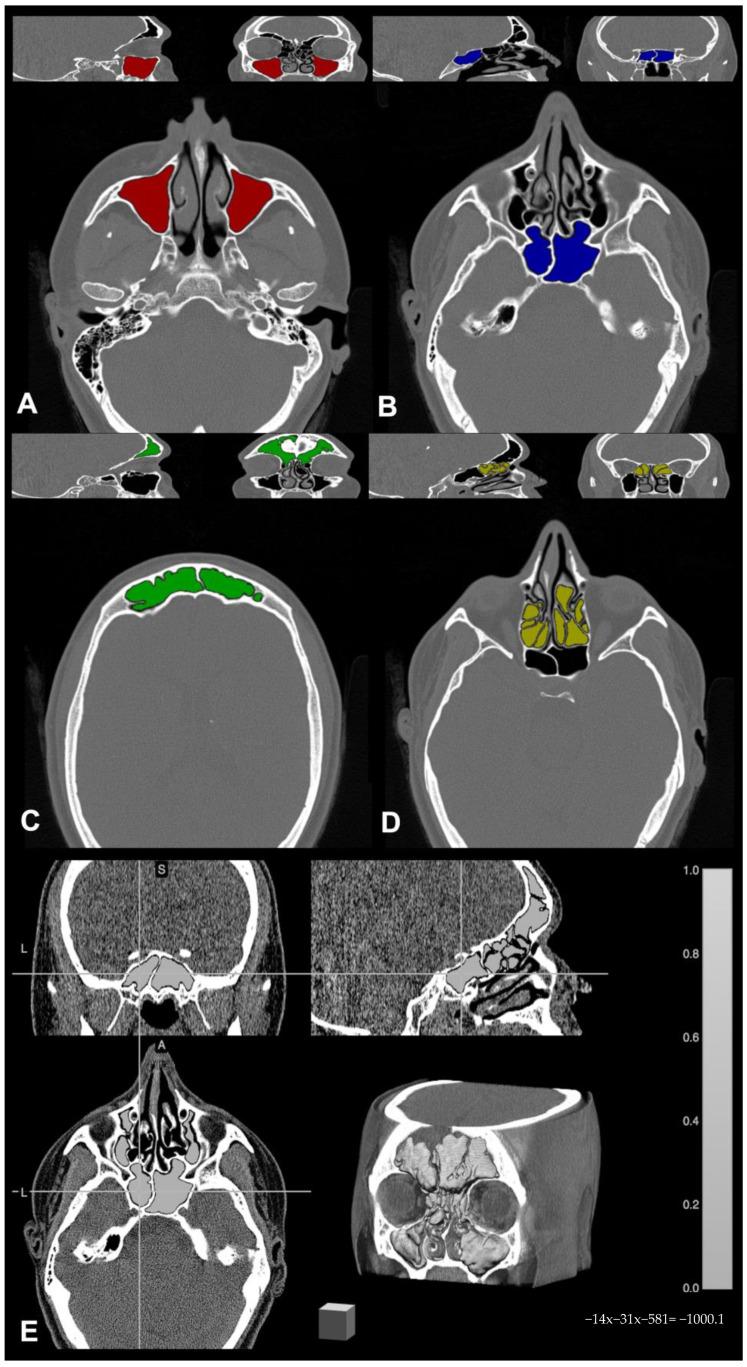

In this retrospective study, we performed a volumetric analysis of paranasal cavity pneumatization in a population of adult patients with cystic fibrosis compared to healthy controls, providing parcel evaluation of each sinus, and analyzing the prevalence of major anatomical sinonasal variants in the two groups. We compared paranasal sinus volumes of 89 adult patients with cystic fibrosis and 144 healthy controls who underwent paranasal sinus computed tomography. Volumes were segmented and extracted on tomographic images using the freely available software MRIcron 2019, then compared using a t-test; the -score test was used to determine whether the two groups differ significantly in terms of major anatomical variants prevalence. Overall sinus volumes in patients with cystic fibrosis patients differ significantly as compared to the healthy population ( < 0.00001). Furthermore, with the only exception of ethmoid sinus pneumatization, which was similar in both populations, all the other sinuses were statistically different. No significant difference emerged concerning anatomical variants' prevalence. Our results further stress the impact of cystic fibrosis on sinus structure in adult patients, better revealing the consequences of the disease on upper airways and in optimizing the management of patients with sinonasal manifestations.

在这项回顾性研究中,我们对成年囊性纤维化患者群体的鼻腔鼻窦气化进行了容积分析,并与健康对照组进行比较,对每个鼻窦进行了分区评估,并分析了两组中主要鼻窦解剖变异的发生率。我们比较了89例成年囊性纤维化患者和144例接受鼻窦计算机断层扫描的健康对照者的鼻窦容积。使用免费软件MRIcron 2019在断层图像上分割并提取容积,然后使用t检验进行比较;使用z分数检验来确定两组在主要解剖变异发生率方面是否存在显著差异。与健康人群相比,囊性纤维化患者的总体鼻窦容积存在显著差异(P<0.00001)。此外,除了筛窦气化在两组中相似外,所有其他鼻窦在统计学上均有差异。在解剖变异发生率方面未出现显著差异。我们的结果进一步强调了囊性纤维化对成年患者鼻窦结构的影响,更好地揭示了该疾病对上呼吸道的影响,并有助于优化鼻窦表现患者的管理。